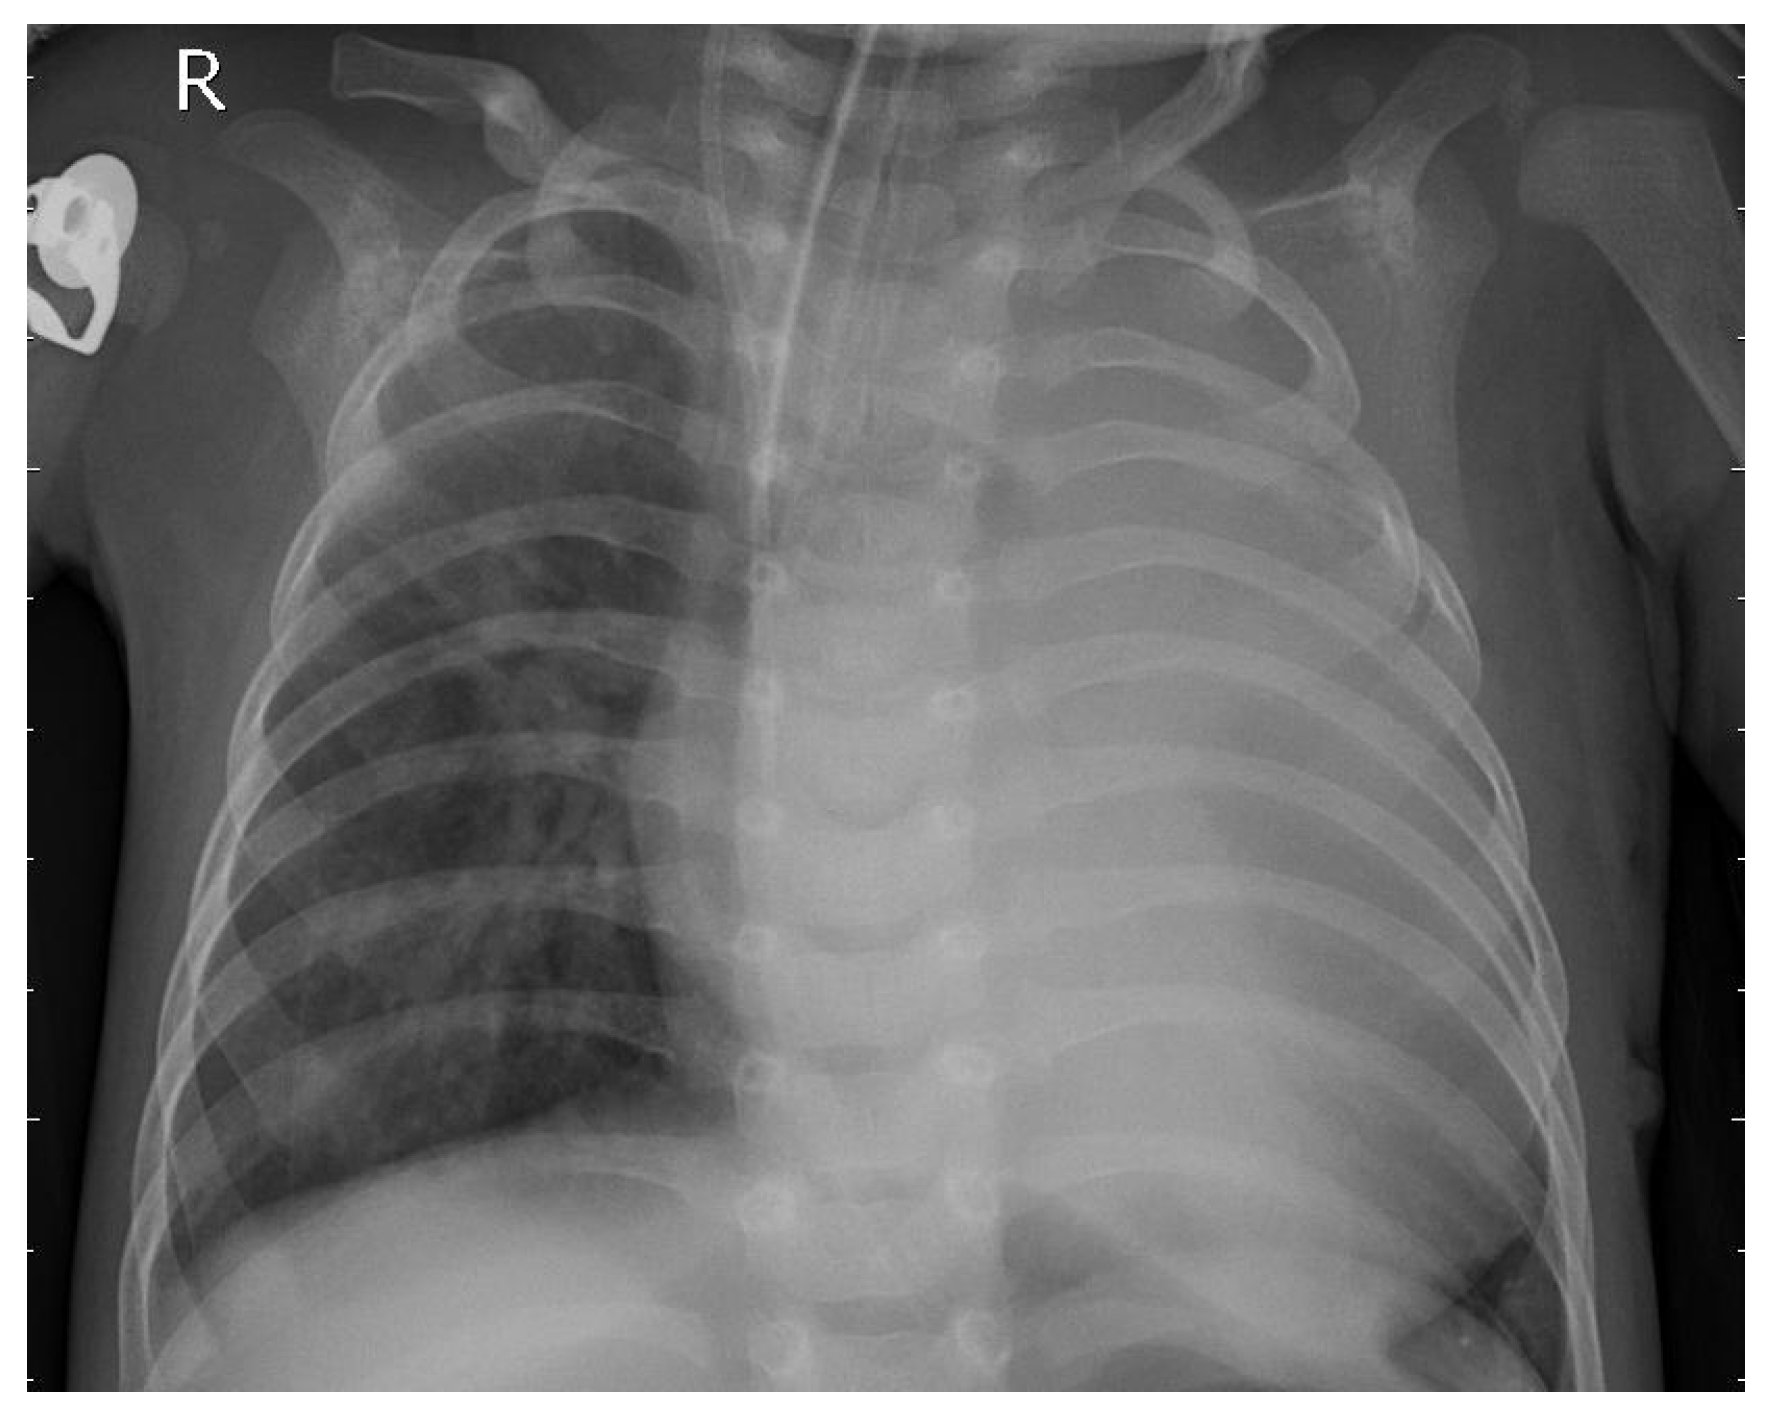

3.1. Dataset

3.2. Preprocessing